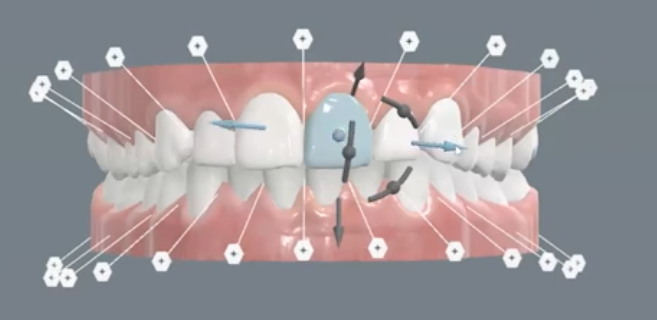

- Les mini-implants en orthopédie dento-faciale :

- Avantages, indications Des Mini-vis.

- Facteurs Influencant le succes.

- Biomecanique des mini-vis sur l’arcade.

- Biomécanique sur gouttières avec et sans extractions